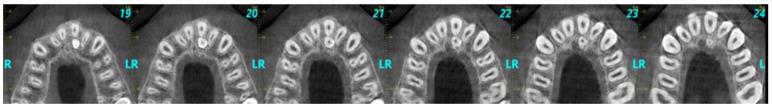

The aim of this retrospective study was to investigate the supernumerary teeth located in the anterior region of the maxilla of non-syndromic Greek children and adolescents, as well as their possible correlation with demographic characteristics and radiographic findings. The study sample comprised cone-beam computed tomography (CBCT) scans from 224 children and adolescents aged up to 18 years. The following parameters were studied: location of supernumerary teeth in the anterior maxillary area, their morphology, their relationship to adjacent anatomical structures and adjacent teeth, and potential implications. Out of the 224 cases 26 (11.6%) presented supernumerary teeth. There was higher prevalence in males than females (61.5% versus 38.5%, respectively). Among the 26 participants diagnosed with supernumerary teeth, one supernumerary tooth was found in 80.8% of children/adolescents, while 19.2% had two supernumerary teeth. The vast majority of supernumerary teeth were impacted (92.3%), and their morphology in 57.7% of cases was conical. A total of 38.5% of cases had normal orientation, 26.9% inverted orientation, 19.2% horizontal orientation, and 15.4% other. The localization was palatal in 84.6%, and the area of localization for 50% of cases was the midline. The prevalence of supernumerary teeth in the studied sample of Greek children and adolescents was 11.6% and tended to appear as single, impacted, conical, and with normal orientation. However, these results should be interpreted with caution, due to the limitations in the sampling strategy and the restricted generalizability of this study. The need for further research to enhance broader applicability for different populations is highlighted. These findings are instrumental for a more comprehensive understanding of the prevalence of supernumerary teeth, contributing to more accurate and individualized dental treatment planning in children and adolescents. This will help to avoid future issues in the patient's dentition.

这项回顾性研究的目的是调查非综合征性希腊儿童和青少年上颌前部区域的多生牙,以及它们与人口统计学特征和影像学表现之间的可能关联。研究样本包括224名18岁及以下儿童和青少年的锥形束计算机断层扫描(CBCT)。研究了以下参数:上颌前部区域多生牙的位置、形态、与相邻解剖结构和相邻牙齿的关系以及潜在影响。在224例病例中,26例(11.6%)出现多生牙。男性患病率高于女性(分别为61.5%和38.5%)。在26名被诊断有多生牙的参与者中,80.8%的儿童/青少年发现一颗多生牙,而19.2%有两颗多生牙。绝大多数多生牙为埋伏阻生(92.3%),57.7%的病例其形态为锥形。共有38.5%的病例方向正常,26.9%倒置,19.2%水平,15.4%为其他方向。84.6%位于腭侧,50%的病例位于中线区域。在希腊儿童和青少年的研究样本中,多生牙的患病率为11.6%,倾向于表现为单个、埋伏阻生、锥形且方向正常。然而,由于抽样策略的局限性和本研究的普遍适用性受限,这些结果应谨慎解释。强调了进一步研究以提高对不同人群更广泛适用性的必要性。这些发现有助于更全面地了解多生牙的患病率,有助于儿童和青少年更准确和个性化的牙科治疗计划。这将有助于避免患者牙列未来出现问题。